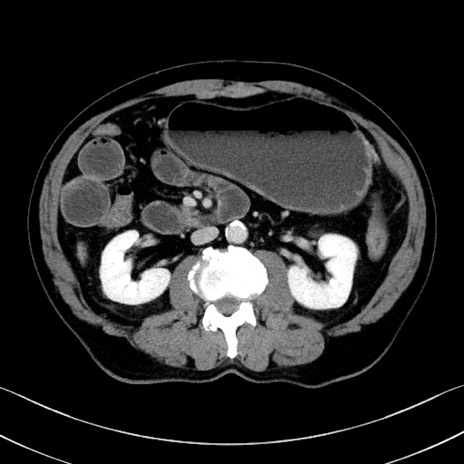

冠状断像

【症例】70歳代 男性

【主訴】腹部膨満、嘔吐

【現病歴】昨日より腹部膨満感出現。本日増悪し、仙痛出現。嘔吐あり、受診。

【既往歴】糖尿病、胆摘後

【身体所見】BP 149/80mmHg、HR 74/min、BT 35.9℃、腹部:膨満、軟、圧痛なし。腸雑音減弱あり。上腹部正中切開瘢痕あり。

【データ】WBC 13500、CRP 1.72